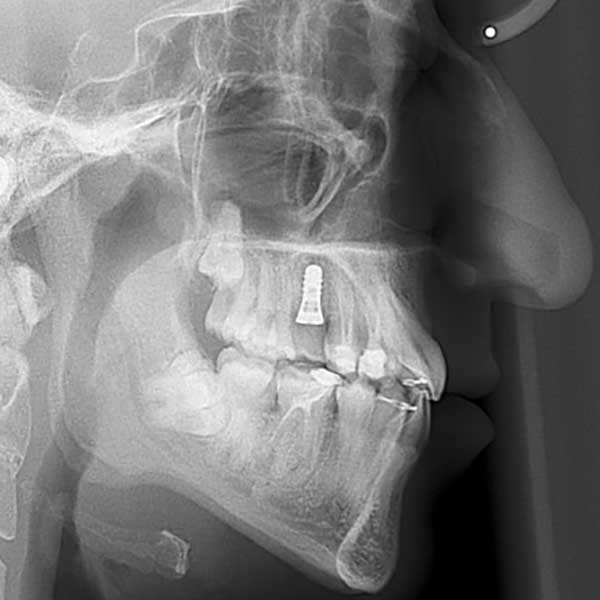

“راجعتني هذه الشابة قبل عدة سنوات وهي تعاني من ازدحام شديد في أسنانها، لدرجة أن أحد أنيابها قد بزغ بشكل مرتفع وبعيد عن مكانه الطبيعي. طلبت مني صديقتنا مساعدتها وترتيب أسنانها ولكن من دون قلع أسنان.

ولحسن الحظ في حالتها كان بالإمكان اجراء المعالجة من دون قلع أسنان، وقد اخترت استخدام التقويم ذاتي الربط (تقويم الدايمون) لأنه يساعد في تحريك الأسنان وتوسيع الفكين. وبالفعل، في نهاية العلاج نجحنا في رصف الأسنان بشكل ممتاز، وبات بإمكان مراجعتنا الابتسام بثقة وسعادة مجدداً.